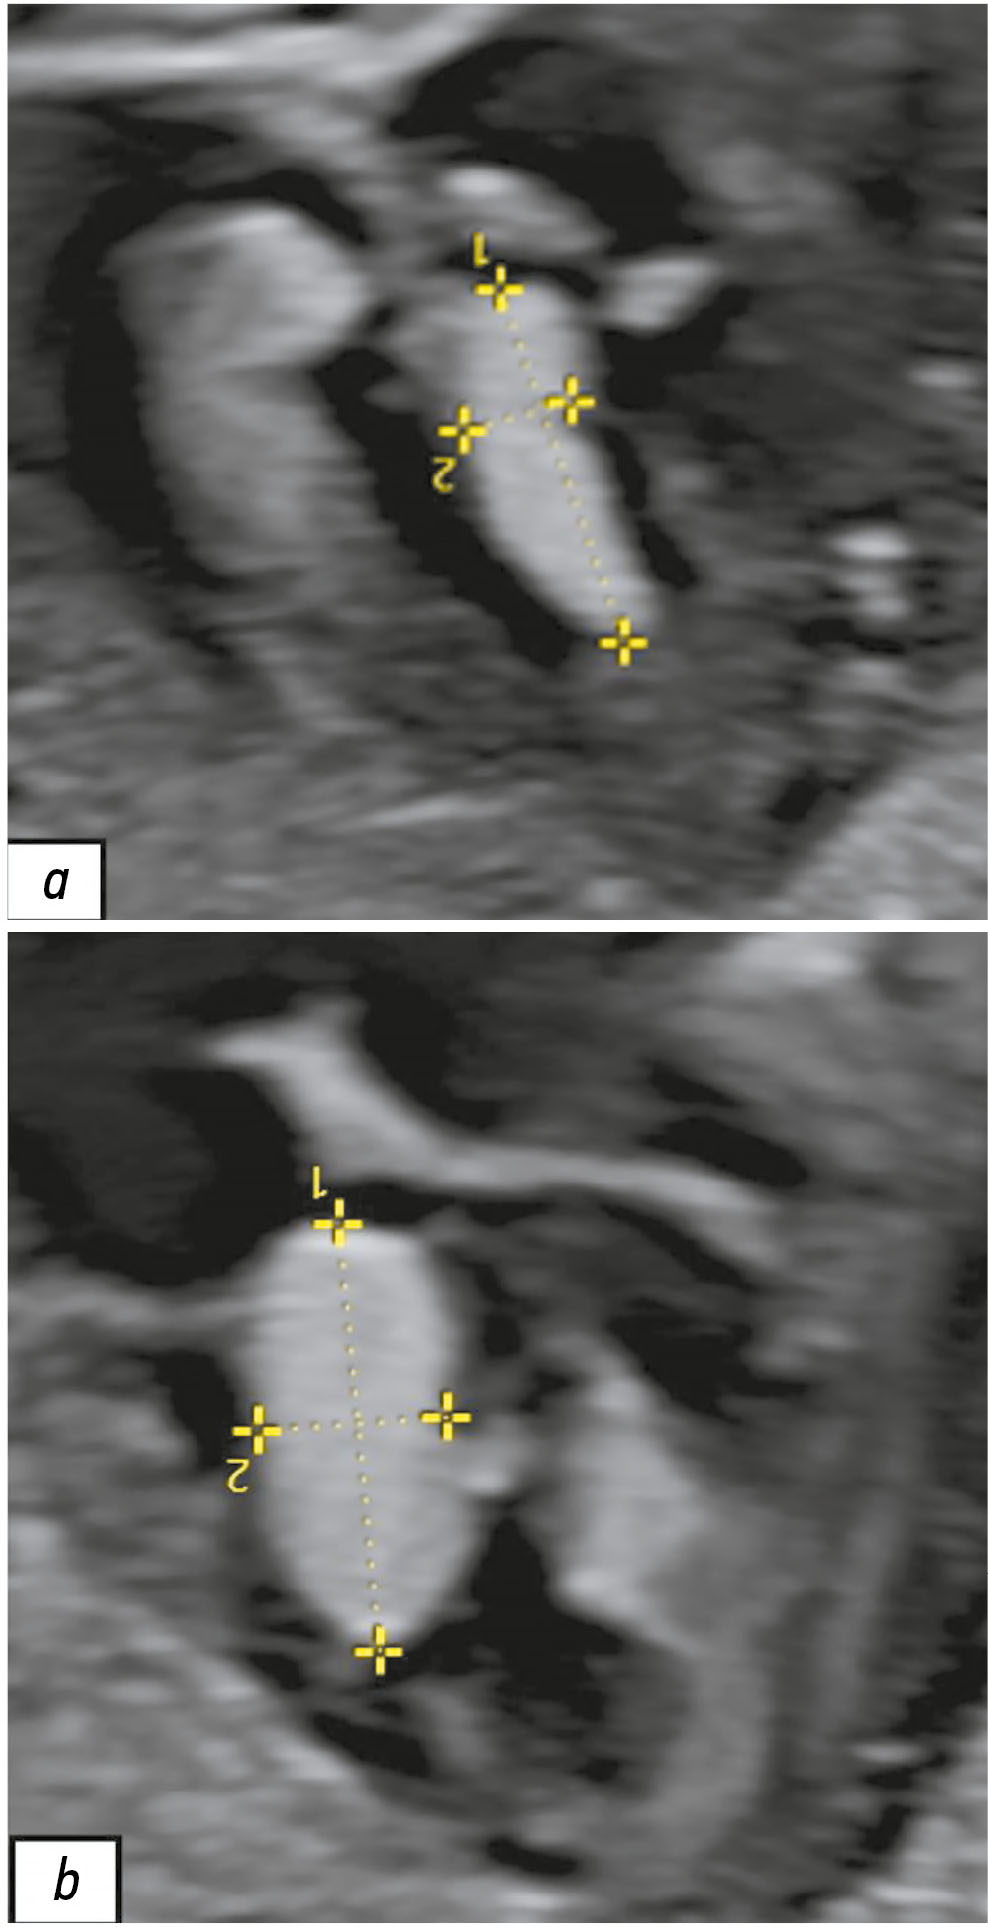

При проведении УЗИ беременной 26 лет на сроке 28 нед. и 2 дня обнаружено наличие объёмных образований в сердце у плода. Выявленные образования не имели кровотока по данным цветового допплеровского картирования и лоцировались в левом желудочке, толще межжелудочковой перегородки и полости правого предсердия (рис. 1). Учитывая наличие сомнительных результатов УЗИ, консилиум в составе врачей-генетиков и врачей-акушеров-гинекологов принял решение провести пренатальную МРТ плода.

Рис. 1. Результаты пренатального ультразвукового исследования сердца плода в III триместре беременности (срок 28 нед. и 2 дня). Визуализируются вытянутой формы гиперэхогенные образования: a — в толще межжелудочковой перегородки; b — в полости левого желудочка.

По данным пренатального УЗИ плода на сроке 39 нед. и 5 дней по-прежнему визуализировались образования: в левом желудочке сердца с размером 16,0×9,1 мм, в толще межжелудочковой перегородки — 11,7×5,9 мм, в полости правого предсердия — 16,8×13,1 мм. При проведении цветового допплеровского картирования кровоток в образованиях не обнаружен, что подтверждает ранние данные о возможной рабдомиоме сердца у плода.